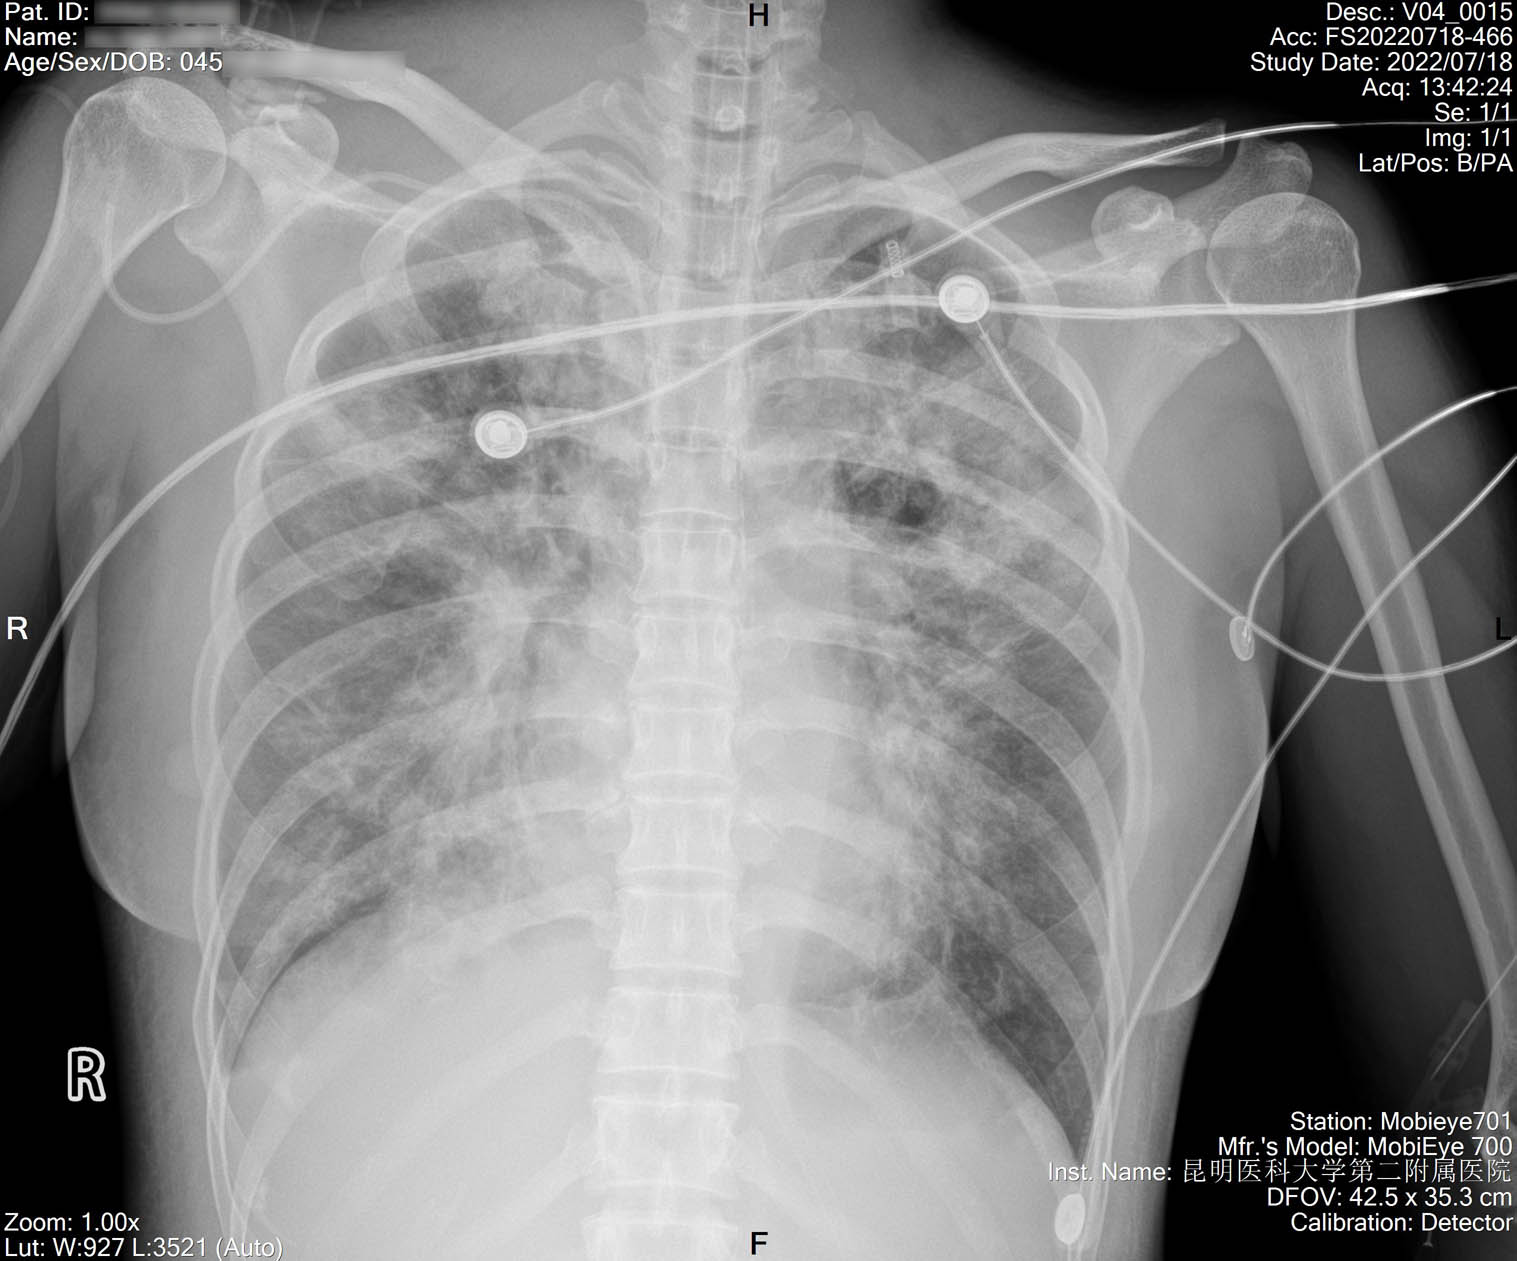

1.2.156.112536.2.560.184134135149163099.1425918311531.40.jpg

2022-07-29_胸片